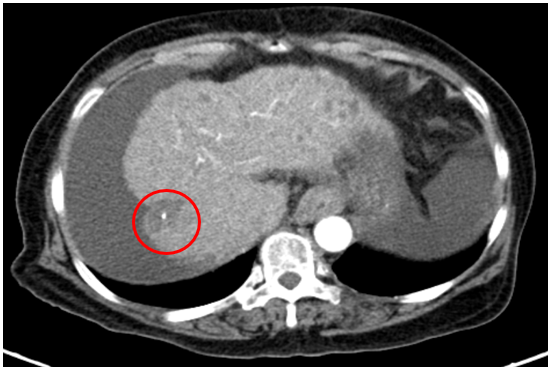

Tháng 4/2025:

Chụp cắt lớp vi tính ổ bụng

Gan: biến đổi hình thái, phì đại HPT I, bờ gan không đều.Nhu mô gan phải có khối giảm tỉ trọng hình chêm kích thước 37x35mm, ranh giới không rõ, co kéo bao gan lân cận, trong có phần tăng tỉ trọng của vật liệu nút mạch, ngấm thuốc kém sau tiêm. Dịch quanh gan 33mm. Dịch tự do ổ bụng

=>Hình ảnh u gan phải sau điều trị hiện không thấy phần ngấm thuốc sau tiêm (Bệnh đáp ứng điều trị nên không có tổ chức ngấm thuốc) (Vòng tròn đỏ)